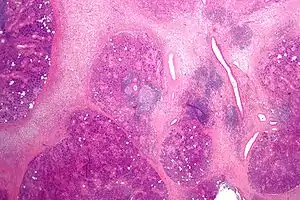

| Micrograph showing chronic sialadenitis. H&E stain. | |

Histologically, chronic sialadenitis can appear from unremarkable to a firm tan with expansion or atrophy of the lobular structure depending on the degree of inflammation and chronicity. Salivary stones (Sialolith) may be evident with cystic dilation of the salivary ducts and periductal fibrosis. Mucus extravasation may also be observed.

Common observations of chronic sialadenitis include chronic inflammatory infiltrate (lymphocytes, plasma cells and macrophages), fibrosis, acinar atrophy, mucous cell metaplasia of the ductal system is observed.

Chronic sialadenitis

Chronic sclerosing sialadenitis has various degrees of inflammation which can include focal lymphocytic sialadenitis to widespread salivary gland cirrhosis with obliteration of acini. This can be a result of obstruction of salivary ducts by microliths (due to associated intercurrent infections), or a result of immune reaction with the formation of secondary lymph follicles.[10] Chronic sclerosing sialadenitis is characterised by presence of three major criteria of[11] dense lymphoplasmacytic infiltrate, storiform pattern of fibrosis and obliterative phlebitis. Minor criteria include phlebitis without obliteration of the lumen and increased numbers of eosinophils. There are two features relatively inconsistent with diagnosis of IgG4-related disease which are the presence of epithelioid cell granulomas and a prominent neutrophilic infiltrate.[11]